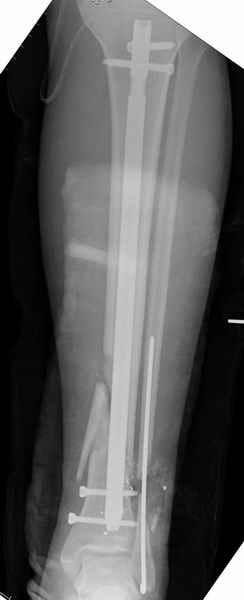

На снимках варианты фиксации малоберцовой:

№ 2-5 при огнестрельном переломе